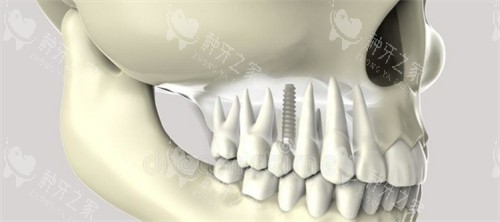

奥齿泰种植体的材质是其耐用性的重要确保。它采用纯钛材质,这种材质不仅重量轻,而且坚固耐腐蚀,能够长期保持稳定的性能。此外,奥齿泰种植体还采用了独特的多重微螺纹设计,这种设计使得植入更加顺利,植入后更稳定,成功概率更高。同时,种植体表面经过多孔纳米氧化钛技术处理,增强了生物活性,减小了排异性,更有效刺激骨细胞发育,加快稳定过程,提高存活率。

奥齿泰种植系统提供了多种型号的种植体,如TSIII超短种植体、TSIV种植体等,以满足不同患者的种植需求。这些种植体适用于各种复杂的口腔情况,如牙槽骨吸收、疏松骨质等。多样化的产品系列不仅为患者提供了更多的选择,也提高了种植的成功概率和稳定性。